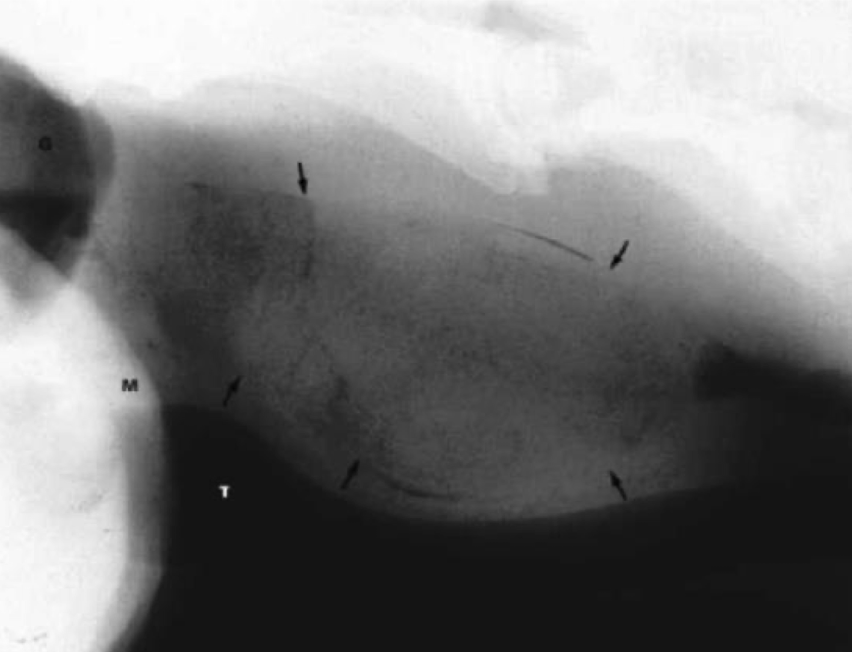

Double contrast study

Negative contrast study

What are the two types of diverticula mentioned in the notes?

A. Traction (true) diverticulum → acquired from contraction of the periesophageal scar tissue, causes outward rotation and tenting of all layers. develops from esophagostomy, second intention healing sites. thicker neck

B. Pulsion (false) diverticulum → protrusion of mucosa and submucosa through a defect in the esophageal muscularis. has a thinner neck. poorer prognosis and will require surgery